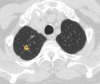

The coronavirus disease 2019 (COVID-19) pandemic is a global health care emergency. Although reverse-transcription polymerase chain reaction testing is the reference standard method to identify patients with COVID-19 infection, chest radiography and CT play a vital role in the detection and management of these patients. Prediction models for COVID-19 imaging are rapidly being developed to support medical decision making. However, inadequate availability of a diverse annotated data set has limited the performance and generalizability of existing models. To address this unmet need, the RSNA and Society of Thoracic Radiology collaborated to develop the RSNA International COVID-19 Open Radiology Database (RICORD). This database is the first multi-institutional, multinational, expert-annotated COVID-19 imaging data set. It is made freely available to the machine learning community as a research and educational resource for COVID-19 chest imaging. Pixel-level volumetric segmentation with clinical annotations was performed by thoracic radiology subspecialists for all COVID-19-positive thoracic CT scans. The labeling schema was coordinated with other international consensus panels and COVID-19 data annotation efforts, the European Society of Medical Imaging Informatics, the American College of Radiology, and the American Association of Physicists in Medicine. Study-level COVID-19 classification labels for chest radiographs were annotated by three radiologists, with majority vote adjudication by board-certified radiologists. RICORD consists of 240 thoracic CT scans and 1000 chest radiographs contributed from four international sites. It is anticipated that RICORD will ideally lead to prediction models that can demonstrate sustained performance across populations and health care systems.